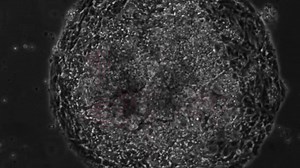

15K views · 394 reactions | Could a new stem cell therapy cure diseas